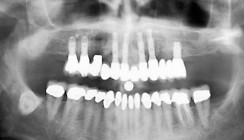

Bei dem 47-jährigen Patienten war ein jahrelang fortschreitender therapieresistenter horizontaler Knochenabbau mit wechselnden akuten Parodontitiden zu beobachten (Abb. 1). Im Jahr 2011 erfolgte zunächst im Oberkiefer die Entfernung aller Zähne und die Eingliederung einer Totalprothese. Da durch die Gaumenbedeckung die Geschmacksempfindung stark beeinträchtigt war, wurden sieben Implantate im Oberkiefer inseriert. Die prothetische Versorgung erfolgte anschließend mit einer abnehmbaren Cover-Denture-Teleskopprothese und verklebten Galvano-Sekundärteilen (Abb. 2 und 3).

2015 kam es durch rezidivierende Parodontitiden und extrem starker Lockerung der Zähne bei dem Patienten zur endgültigen Therapieplanung des Unterkiefers (Abb. 4). Die Unterkieferschneidezähne mussten aufgrund der starken Lockerung vorab entfernt werden. Aufgrund des Würgereizes wurde eine Implantation in Intubationsnarkose vorgesehen, welche die Entfernung aller restlichen Zähne mit gleichzeitiger Implantation und Insertion von zwei Interimsimplantaten, um die Prothese zu stabilisieren, beinhaltete. Auf Abbildung 5 ist gut zu erkennen, dass die Implantatachsen später erheblich von der Stellung der ursprünglichen Zähne abweichen werden. Eine Implantation in der Achse der vorhandenen Zähne war nicht möglich, da es zu einer lingualen Perforation gekommen wäre. Dennoch musste eine Lösung gefunden werden, die dem Patienten später den entsprechenden Zungenraum wiedergibt. Eine prothetische Versorgung mit Teleskopkronen kam nicht infrage, da ansonsten der Zahnbogen auf jeder Seite um mindestens 5 mm kleiner geworden wäre. In der Implantatchirurgie wurden fünf definitive Implantate auf der linken Seite und vier definitive Implantate auf der rechten Seite sowie zwei Hilfsimplantate für die sofortige Wiederherstellung und die Belastung mit einer temporären Sofortprothese eingesetzt (Abb. 5 und 6).